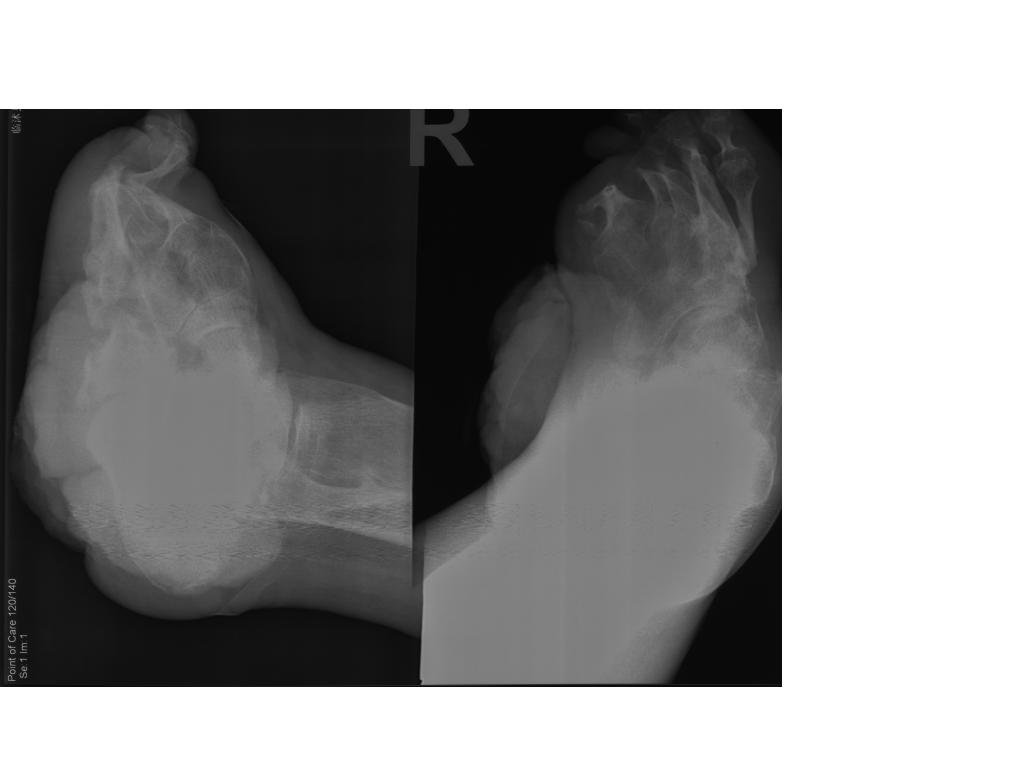

老年男性,麻风病患者已治愈,左下肢议肢,现发现右足踝部较大溃疡半年余,恶臭,专科检查见右足踝部有一菜花样肿物,触之易出血,病理高分化鳞癌。全身体格检查尚可。请教肿瘤和麻风病的关系?菜花样肿物

1、麻风病骨改变。2、软组织皮肤鳞状细胞癌。

1、麻风病骨改变。2、踝部软组织皮肤鳞状细胞癌,与慢性溃疡经久不愈及感染有关。

1、麻风病骨改变。2、踝部软组织皮肤鳞状细胞癌,与慢性溃疡经久不愈及感染有关。两者没有关系